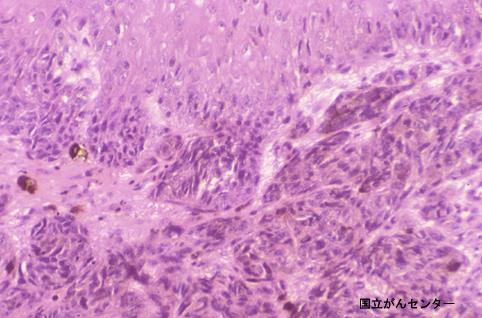

Múltiple Melanoma Maligno de Esófago acompañado de metástasis intramural

[Image-ID:4157]

Melanoma Maligno/

esófago/inferior

Micro

Tipo 0(tipo superficial)/Tipo I(Isp)

20 - 24

sm

presente(simultáneo)